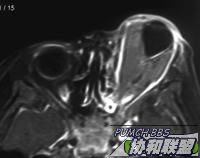

患者男8岁。左眼球突出2周,疼痛明显。当地治疗无效。就诊时检查左视力无光感,眶压明显增高,眼球固定,眼底视盘水肿,散在出血

MRI检查如图